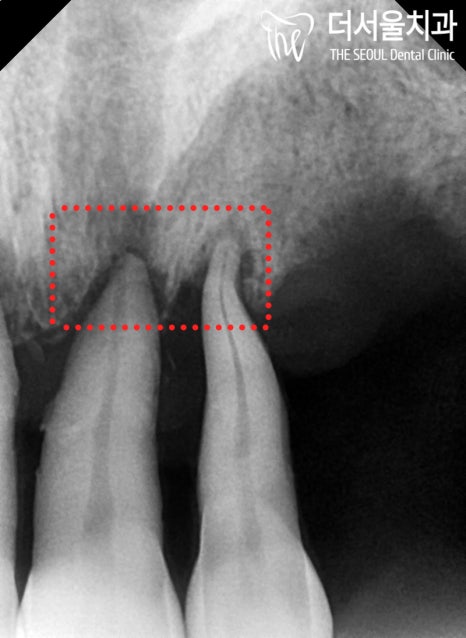

2. 뼈 상태 체크

치아가 있는 곳을 제외하고는

잇몸뼈는 거의 없는 상태입니다.

특히 윗부분은 상악동의 막과

거의 손톱만큼의 거리가 될 정도로

정말 얇은 것을 볼 수 있죠.

끝에 있는 어금니는

뿌리만 살짝 걸치고 있을 정도로

남아있는 뼈가 없는 상태였습니다.

또, 이미 흔들림이 커서 발치를 해야 되었구요.

그리고 앞니 역시 마찬가지로

뿌리 끝에만 걸치고 있는 상황이었습니다.

결국 모두 발치하기로 하며